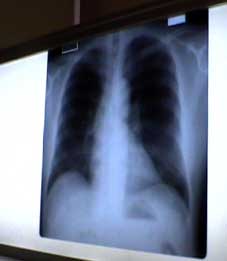

| 私のレントゲン写真、きれいなもんだ。 | ||||||||||||||||||||||||